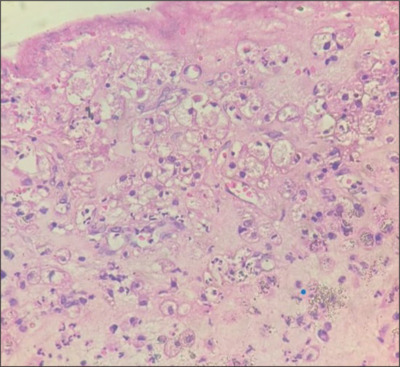

Xantho-granulomatous pleuritis: A rare histopathological entity with diagnostic and therapeutic challenges.

黄斑肉芽肿性胸膜炎:一种罕见的组织病理实体,诊断和治疗具有挑战性。